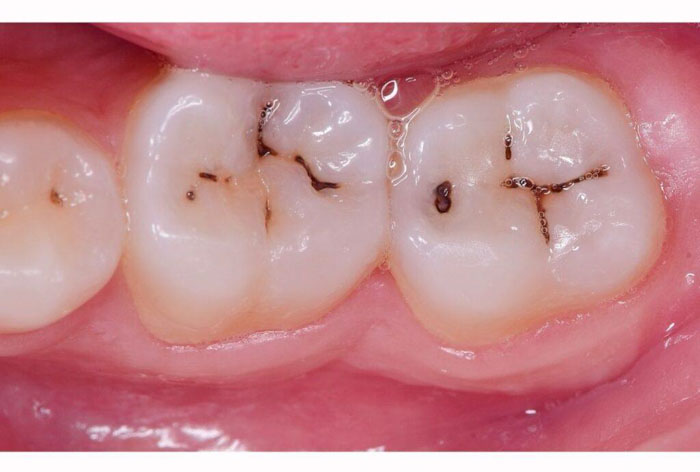

Những đốm đen nhỏ xuất hiện trên răng – đặc biệt ở răng hàm – không chỉ làm mất thẩm mỹ mà còn có thể là dấu hiệu sớm của sâu răng. Nhiều người thường nghĩ do mảng bám hoặc đồ ăn bám lại, nhưng nếu chải răng không sạch được, đó rất có thể là tình trạng sâu men.

Đây là giai đoạn đầu của sâu răng. Ở giai đoạn này, tổn thương chỉ mới xảy ra ở lớp men răng và hoàn toàn có thể phục hồi nếu bạn được thăm khám và điều trị sớm.

Trước và sau điều trị đốm đen trên răng tại Nha Khoa Như Ngọc